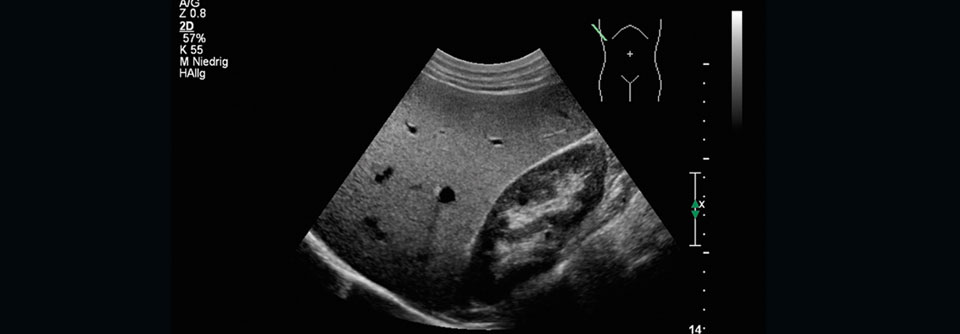

Menschen mit Typ-2-Diabetes neigen dazu, eine nicht-alkoholische Fettleber (NAFLD) zu entwickeln. Umgekehrt ist NAFLD mit einem zweifach erhöhten Risiko für einen Typ-2-Diabetes assoziiert. Verlieren Patienten an Gewicht, können sie damit auch ihre Fettleber verringern – in der Praxis ist dies in vielen Fällen aber nur schwer zu erreichen.

Es gibt jedoch Hinweise, dass sich SGLT2-Hemmer dafür eignen könnten, eine NAFLD zu behandeln. In einer randomisierten Phase-4-Studie untersuchten die Forscher um Dr. Sabine Kahl vom Deutschen Diabetes-Zentrum (DDZ) an der Heinrich-Heine-Universität Düsseldorf gemeinsam mit Wissenschaftlern des…